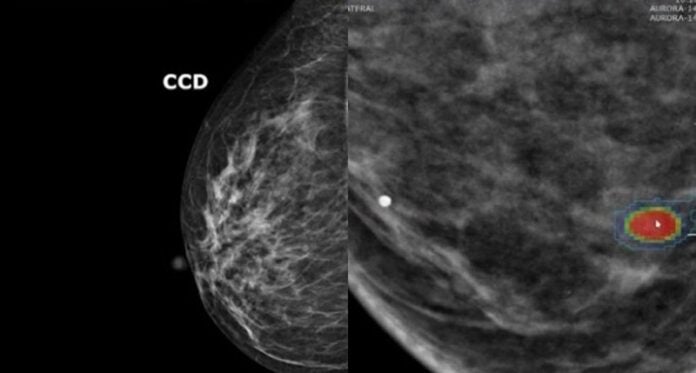

Agora um novo algoritmo promete reorientar a triagem: um modelo de inteligência artificial (IA) consegue avaliar com elevada precisão, simplesmente analisando dados de imagens de mamografia, o risco de uma pessoa desenvolver câncer de mama nos próximos cinco anos.

Num estudo, mulheres identificadas pelo algoritmo como tendo alto risco de desenvolver câncer de mama de fato apresentaram uma probabilidade significativamente maior de desenvolver a doença do que mulheres identificadas pela IA como tendo “risco normal”.

“Essas mulheres desenvolveram câncer de mama quatro vezes mais frequentemente do que aquelas com baixa pontuação na IA”, diz Kuhl, que é a autora principal do estudo. “Com a IA que desenvolvemos, podemos prever com muito mais precisão que uma mulher desenvolverá câncer de mama nos próximos cinco anos – com base em mamografias que não apresentam sinais da doença.”

O avanço crucial, em sua opinião, é que “a IA pode decidir em segundos se uma mulher precisa ou não de uma ressonância magnética para detecção precoce”.